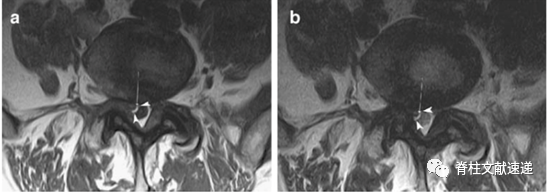

术中已经证实异常神经根。三角所示为新月形脂肪。

三角所示为角形征,箭头所示为新月形脂肪。